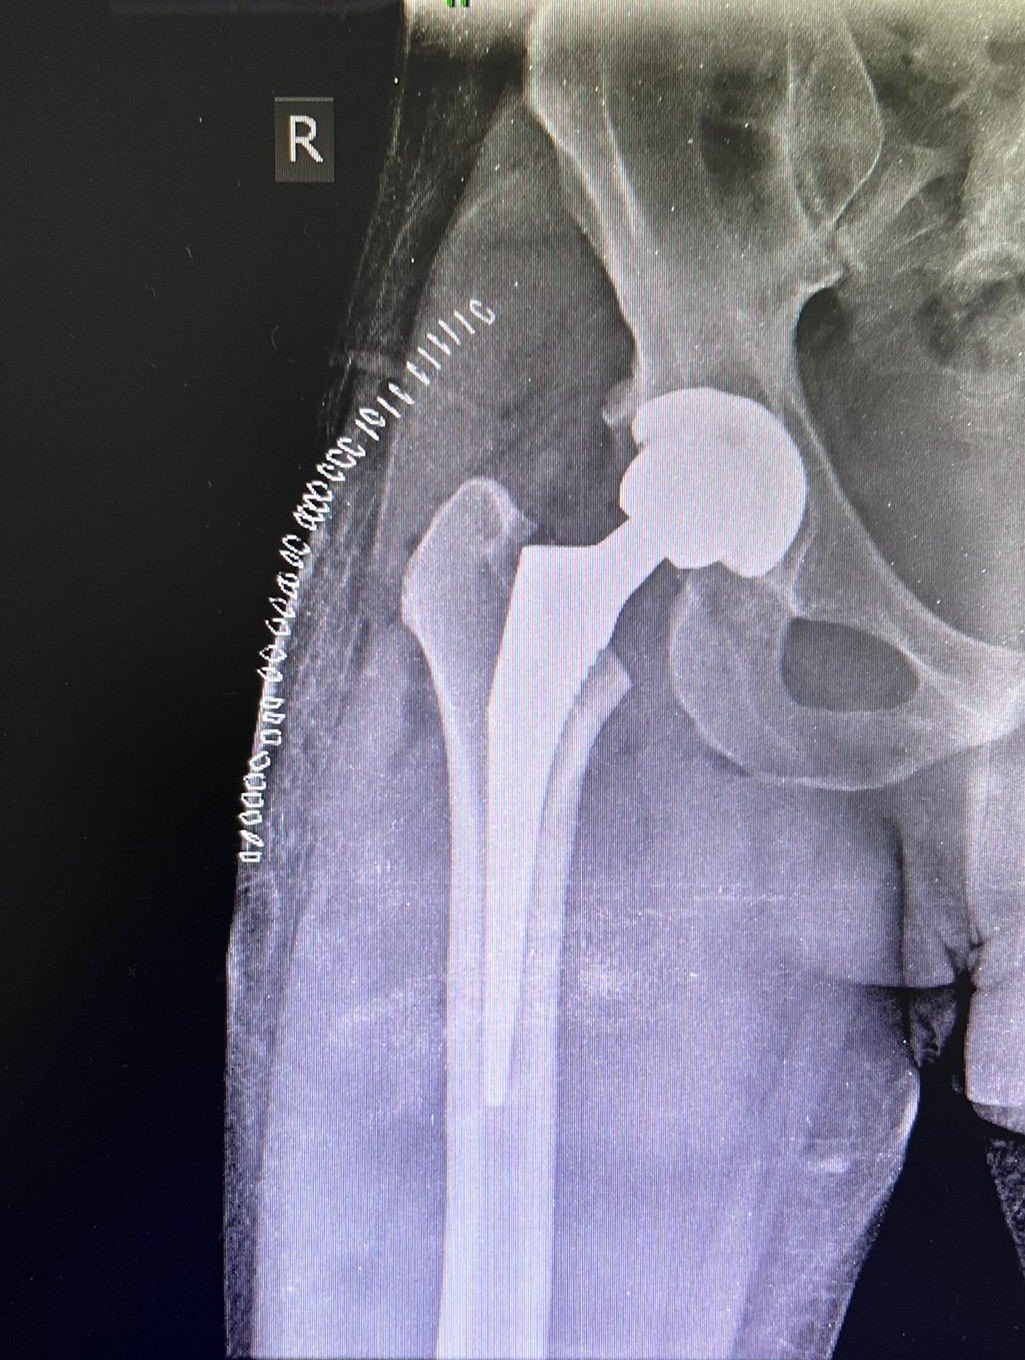

Post-Op X-Ray